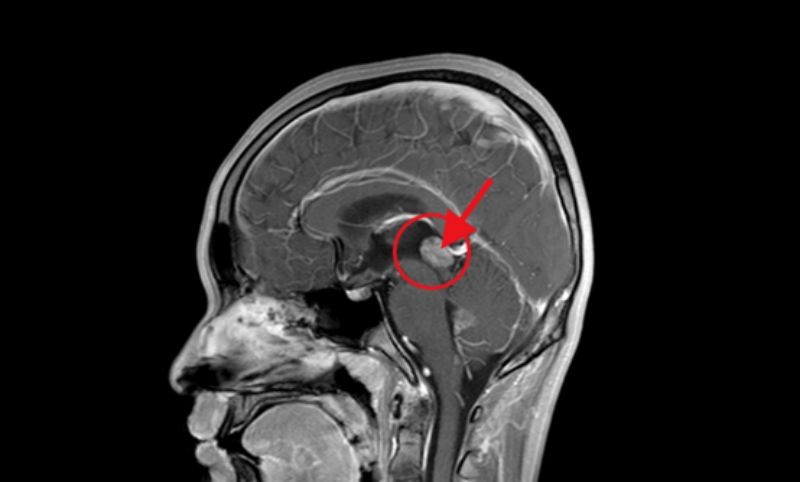

原来家住广西桂林的17岁小伙小李突发眩晕后来到自治区南溪山医院就诊,通过检查发现小李的脑子深处长有一个鹌鹑蛋大小的肿瘤,这个肿瘤压迫周围脑组织如果继续任其发展下去将会造成不可挽回的结果。

检查结果显示小李的脑部有一鹌鹑蛋大小的肿瘤